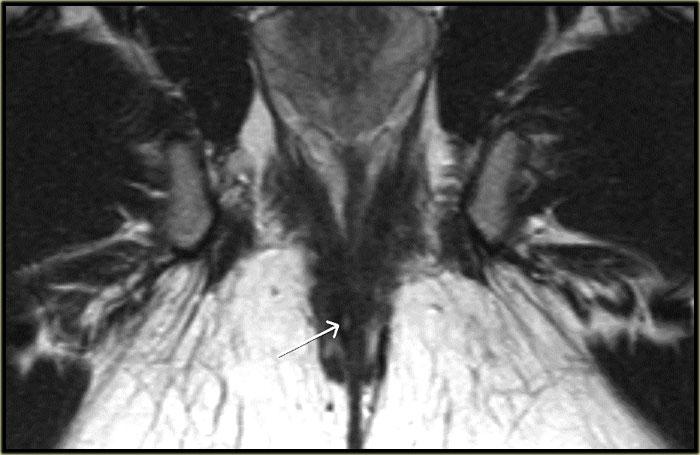

Bên trái là một ví dụ về rò trên cơ thắt.

Có hai đường rò trong vùng hố ngồi-hậu môn.

Đường rò bên phải chạy qua cơ mu-trực tràng (dấu hoa thị) và lỗ mở niêm mạc nằm ở

mức đường lược (mũi tên đen).

Rò ngoài cơ thắt

Bên trái là hình ảnh coronal chuỗi xung T2W của một ổ áp xe nhỏ trong hố ngồi-hậu môn trái, đường rò chạy xuyên qua cơ nâng hậu môn.

Do đó, đường rò nằm phía trên phức hợp cơ thắt và thuộc loại ngoài cơ thắt.